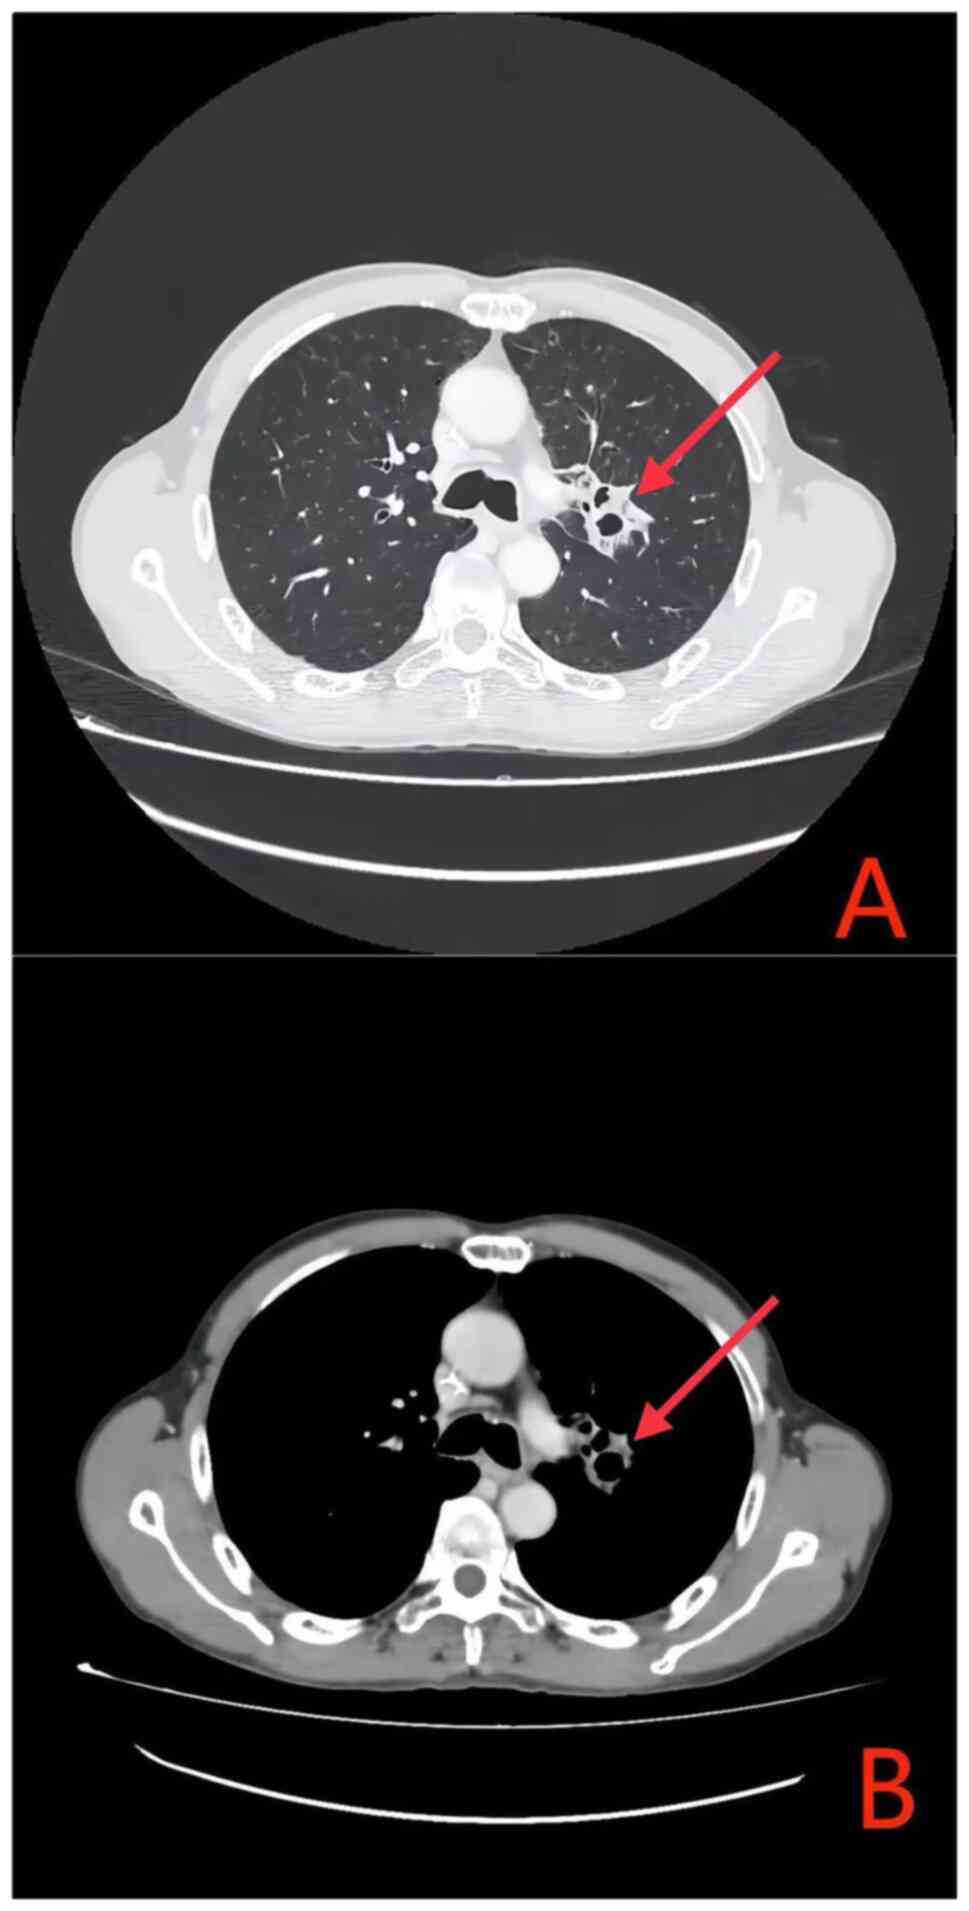

In July 2023, the patient began treatment with a combination of albumin-bound paclitaxel, cisplatin and a PD-1 inhibitor. Tislelizumab 200 mg was administered via intravenous drip on Day 1. Paclitaxel (albumin-bound) 395 mg was administered via intravenous drip on Day 2. Cisplatin 110 mg was administered via intravenous drip from Day 2 to Day 3, divided into two administrations. The treatment cycle is 21 days, and this is the first cycle. Subsequently, in August 2023, a comprehensive re-evaluation of the hepatic and renal function of the patient, along with electrolyte profiling, revealed hyperkalemia, hyperphosphatemia, hyperuricemia, hypocalcemia and signs of acute renal impairment (Table I); however, the patient remained asymptomatic for arrhythmia, tetany, muscular spasms, hypotension, nausea, vomiting, abdominal discomfort or oliguria. Based on consensus guidelines from the TLS expert panel (9), a diagnosis of laboratory-confirmed TLS was considered. Treatment included rectal administration of Shenkang Shuan (4 g (4× daily), oral Niuduqing granules 5 g for kidney protection (3× daily) Until renal function returns to normal, oral cyclosilicate sodium powder to reduce potassium levels (3× times daily, adjusted to 5 g orally 3× daily to maintain stability once the blood potassium levels normalized), and febuxostat 20 mg (once daily) to decrease uric acid levels. Fluid replacement and dynamic monitoring of liver, kidney and heart function were initiated, along with symptomatic treatment [Administer intravenous infusion of 0.9% sodium chloride injection at a dosage of 3 l/m2 daily, and maintain urine output at a rate greater than 100 ml/(m2•h)]. After fluid replacement, urine alkalinization, electrolyte correction and kidney protection, the parameters of the patient improved (Table I). In accordance with the monitoring recommendations outlined in the National Comprehensive Cancer Network® guidelines during initial therapy (10), due to the manifestation of TLS symptoms in the patient, a timely assessment of any changes in the condition of the patient was imperative. Therefore, following a single cycle of chemotherapy combined with PD-1 immunotherapy, radiological reassessment performed at 4 weeks post-treatment demonstrated a marked decrease in the size of both the primary lung lesion and the metastatic lymph nodes when compared with the baseline prior to treatment (Fig. 3). The treatment efficacy was classified as a partial response (PR) based on the Response Evaluation Criteria in Solid Tumours (RECIST) 1.1 criteria (11) (Figs. 2 and 3). From the second cycle onwards, the chemotherapy drug was adjusted to albumin-bound paclitaxel + carboplatin (Tislelizumab 200 mg was administered via intravenous drip on Day 1. Paclitaxel (albumin-bound) 395 mg was administered via intravenous drip on Day 2. Carboplatin 440 mg was administered via intravenous drip on Day 2. The treatment cycle is 21 days). Upon completion of the systematic treatment, the efficacy evaluation according to RECIST 1.1 criteria was classified as a PR (Fig. 4). As of April 2024, the patient's condition remains stable.

Figure 4.

After completion of the systematic treatment. (Chest contrast-enhanced CT: (A) Upon comparison with pretreatment status, the primary tumor has demonstrated marked regression. (B) Metastatic lymph nodes have exhibited significant downsizing relative to the pretreatment condition).